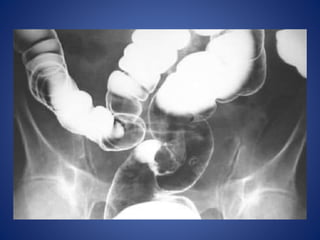

Volvulus x ray: Sigmoid volvulus -

'coffee bean' sign

The sigmoid colon is very dilated because it is twisted at the root of its

mesentery in the left iliac fossa (LIF)

The twisted loop of sigmoid colon is said to resemble a coffee bean